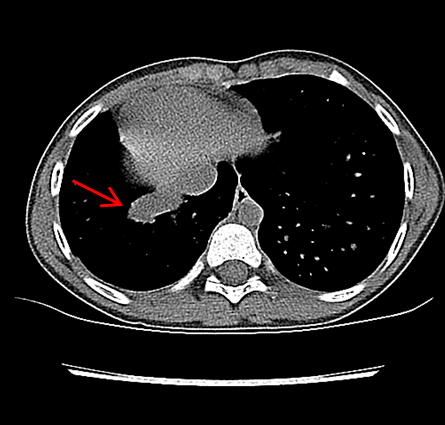

Routine laboratory analysis, including a complete blood count and metabolic panel, is normal. A postero-anterior chest roentgenogram is shown in Figure 1. Chest computed tomography (CT) without IV contrast (Figure 2), and gadolinium enhanced magnetic resonance angiogram (Figures 3 and 4) are also obtained. A decision is made to perform a cardiac catheterization (Figures 5 and 6) for further evaluation.

Figure 2

The red arrow (Figures 7, 8, 9, and 11) shows a large scimitar vein. Chest CT (Figure 8) shows partial anomalous pulmonary venous return from the right lower pulmonary vein into the inferior vena cava (IVC) and right-sided pulmonary hypoplasia with consequent dextro-position of the heart into the right hemithorax. The gadolinium-enhanced angiography cardiac magnetic resonance imaging (MRI) (Figure 9) with three-dimensional reconstruction (Figure 10, Video 1) confirms the diagnosis, which shows aortopulmonary collaterals from the descending abdominal aorta to the right lower lung lobe (one dot), large anomalous pulmonary vein, the scimitar vein (two dots), draining the right lower lung to the IVC (three dots). The right heart is within normal limits for size.